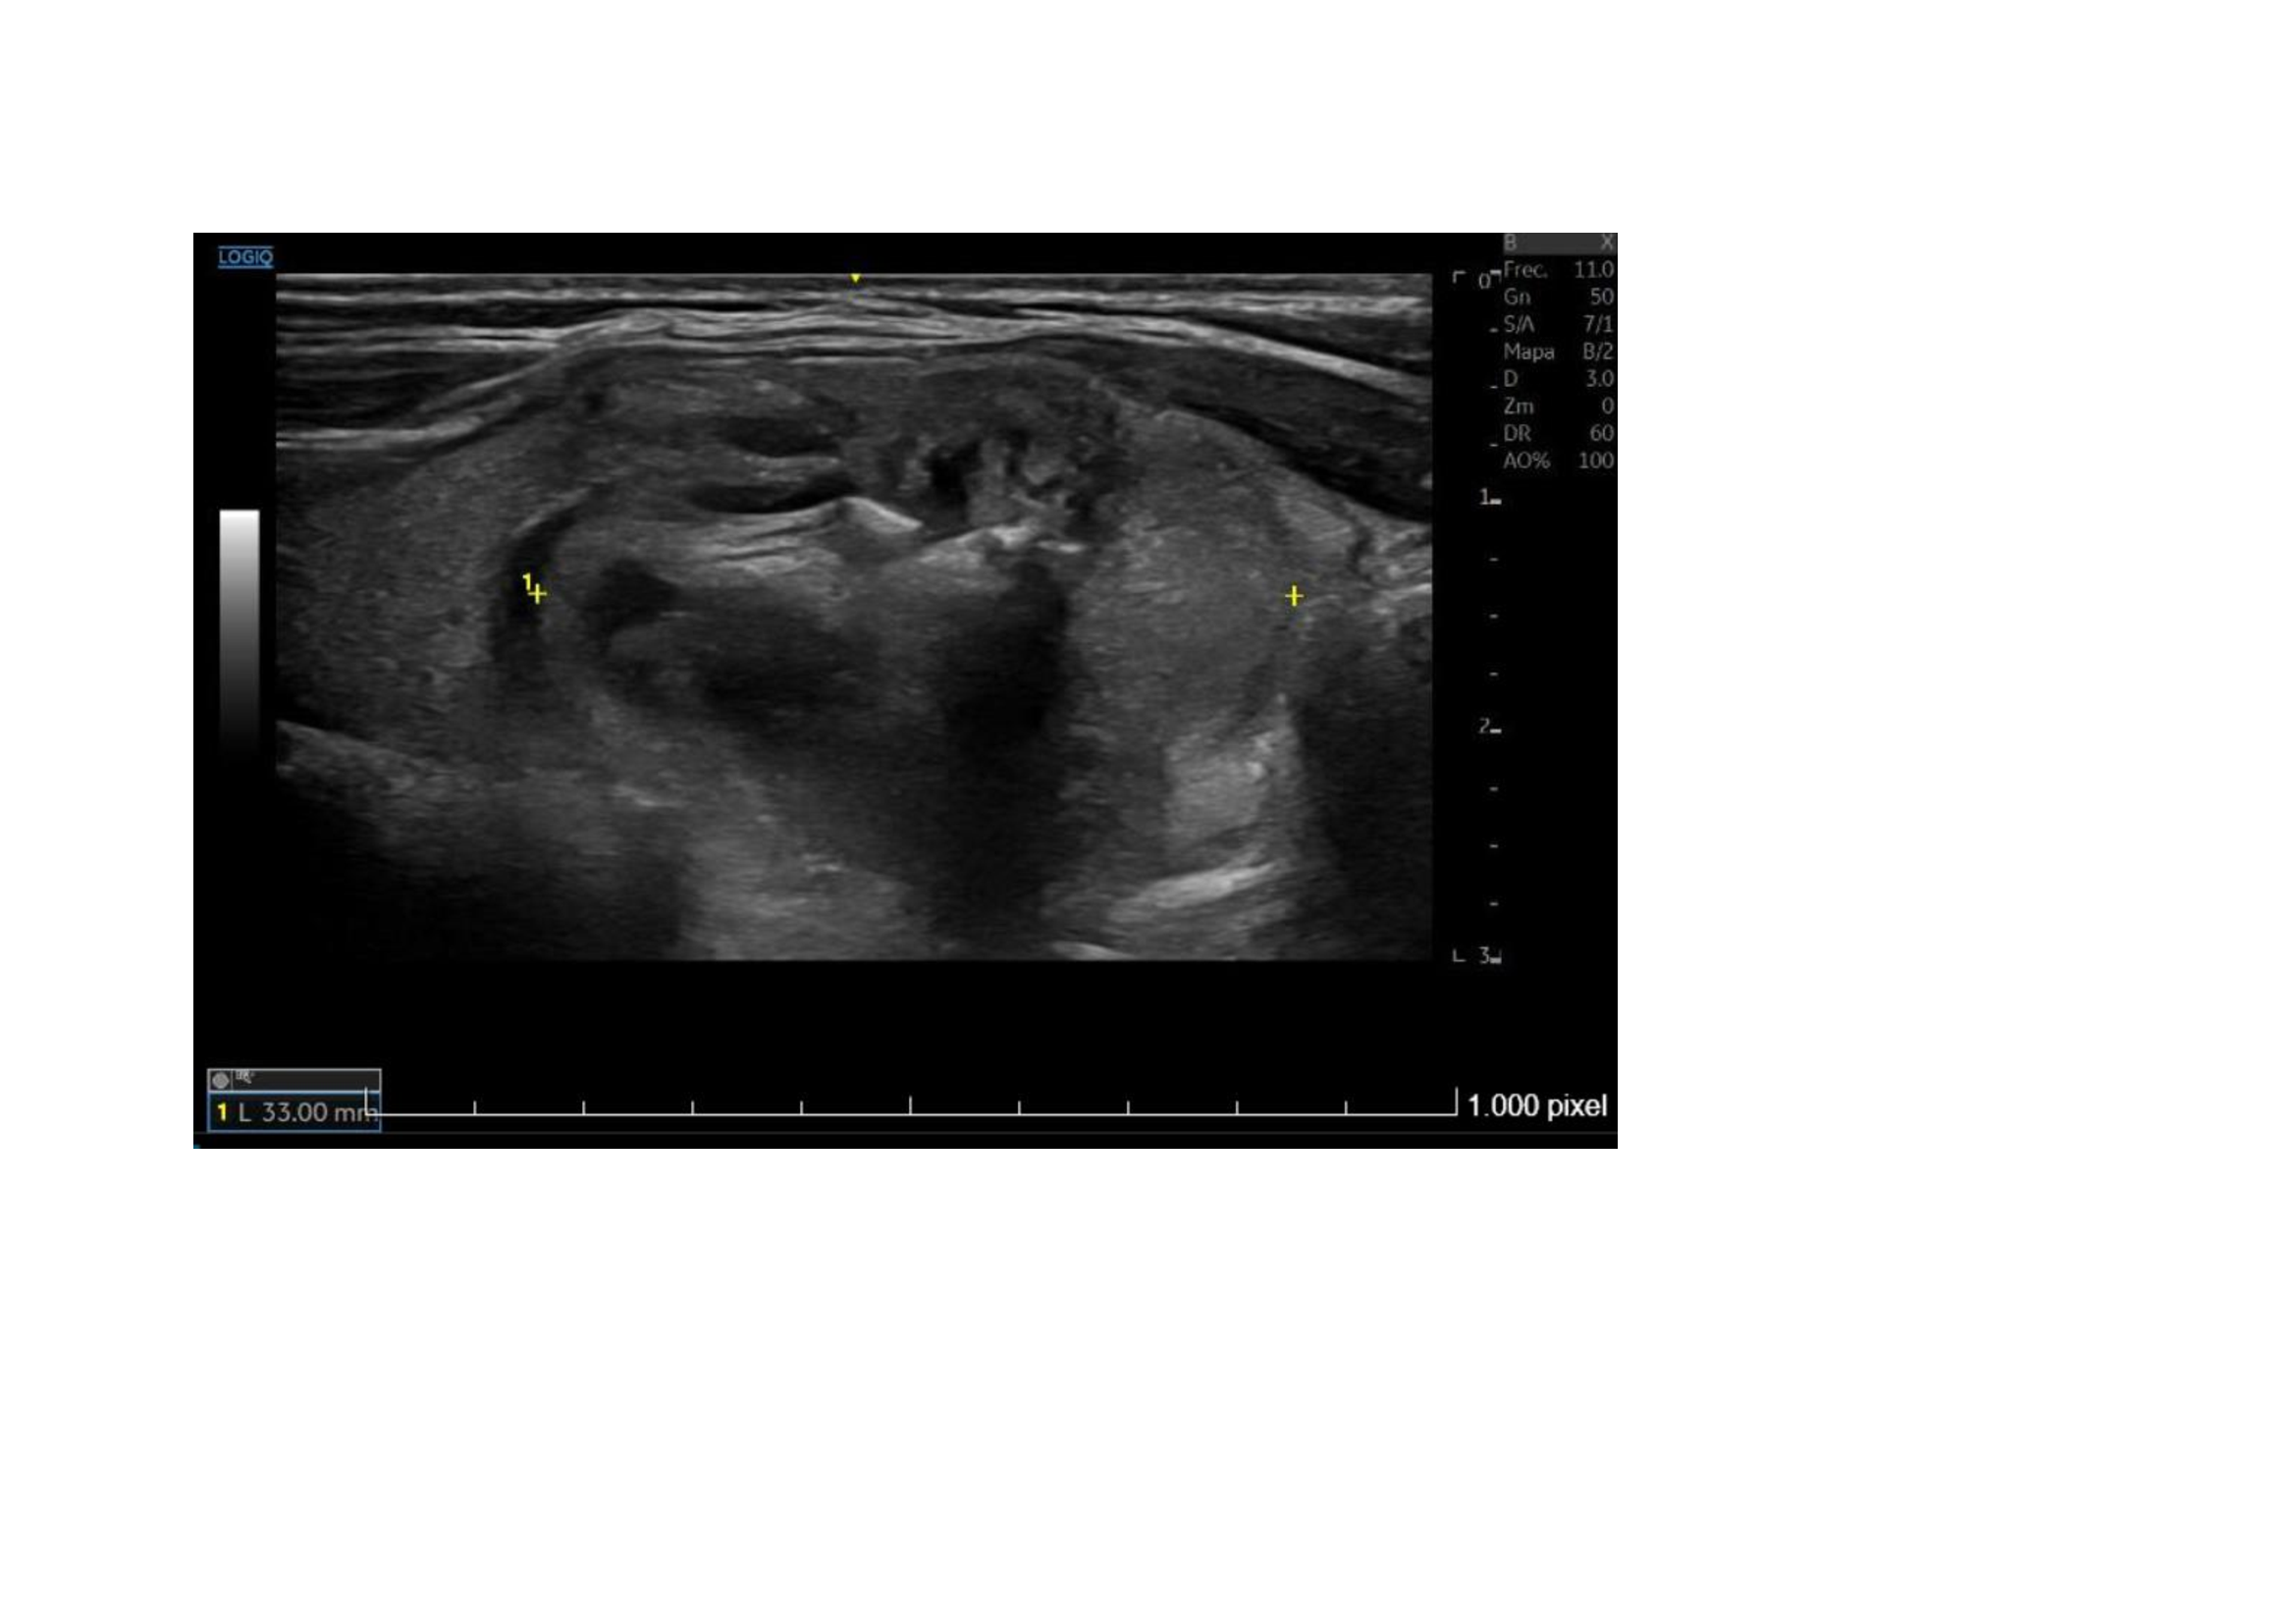

Ecografía Hospital: Lóbulo tiroideo derecho aumentado de tamaño (2,2 cm de diámetro anteroposteior), por la presencia de un nódulo sólido, heterogéneo, levemente hipoecoico, bien definido, con áreas de degeneración quística y calcificaciones groseras en su interior, de 22 x 21 x 33 mm. Resto del tiroides sin alteraciones. No se aprecian adenopatías cervicales. Glándulas salivares sin alteraciones. Conclusión: Nódulo en lóbulo tiroideo derecho, único, TIRADS 4.